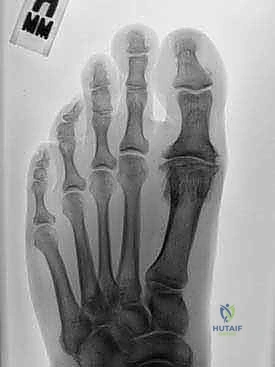

Radiographic Evaluation

Standard weight-bearing radiographs of the foot are mandatory. The anteroposterior view evaluates joint space narrowing, subchondral sclerosis, and the presence of lateral osteophytes or loose bodies. The lateral view is critical for assessing the size of the dorsal osteophyte and the degree of metatarsus primus elevatus. An axial sesamoid view must be obtained to evaluate the articulation between the sesamoids and the plantar metatarsal head; severe sesamoid arthritis is a relative contraindication to motion-preserving surgery.